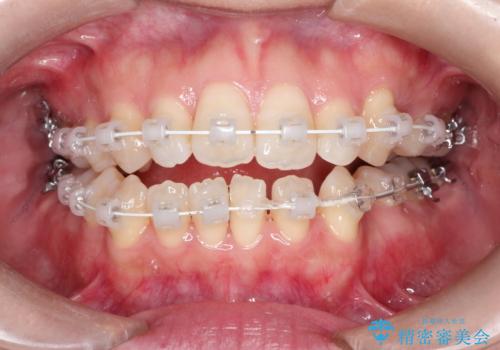

前歯がガタガタで咬めない ワイヤーによる抜歯矯正で整った歯並びへ

- 前歯がガタガタなのと、前歯でものが噛めないことを主訴に来院されました。

前歯の叢生があり、上下の前歯が接触していない開咬という状態でした。

左側の上下の前から4番目の歯を抜歯して、矯正することとしました。

装置は表側のワイヤーを選択されました。

ガタガタがなくなり、上下の前歯が接触すようになり、見た目とともに咬みやすくすることができました。